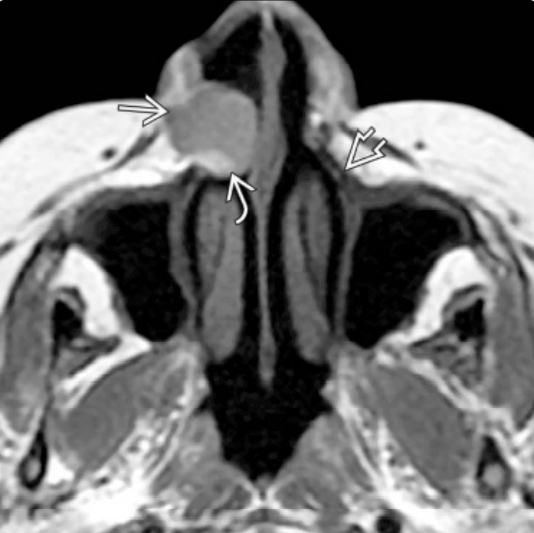

Κύστη του Ρινοϋπερώιου Πόρου

Οι κύστεις αυτές εντοπίζονται εντός του αντίστοιχου πόρου ή εντός των μαλθακών ιστών στη μέση γραμμή της άνω γνάθου, ανάμεσα στους κεντρικούς τομείς, στο στόμιο του πόρου.

Η κύστη του ρινοϋπερώιου πόρου αναπτύσσεται από τον πολλαπλασιασμό επιθηλιακών υπολειμμάτων από το ζεύγος των εμβρυϊκών ρινοϋπερώιων πόρων που πορεύονται εντός του τομικού πόρου.

Πρόκειται για μια σχετικά συχνή κύστη, που μπορεί να εμφανιστεί κλινικά ως συμμετρική διόγκωση της μέσης γραμμής της υπερώας ή ακτινογραφικά σαν ακτινοδιαυγή περιοχή της μέσης γραμμής. Η πλειοψηφία των περιπτώσεων εμφανίζεται ανάμεσα στην 4η και 6η δεκαετία της ζωής και είναι συχνότερη στους άνδρες με αναλογία 3:1.

Οι περισσότερες περιπτώσεις είναι ασυμπτωματικές, με τη διόγκωση να είναι το κλινικό σημείο που οδηγεί στην αναγνώριση της κύστης.

Επιμόλυνση της κύστης μπορεί να οδηγήσει στην εμφάνιση συμπτωμάτων. Σχηματισμός συριγγίου μπορεί να εμφανιστεί μάλλον στο προέχον σημείο της υπερώιας θηλής.